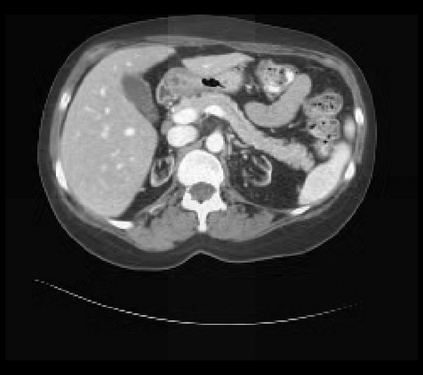

It is imperative to ensure the robustness of deep learning models in critical applications such as, healthcare. While recent advances in deep learning have improved the performance of volumetric medical image segmentation models, these models cannot be deployed for real-world applications immediately due to their vulnerability to adversarial attacks. We present a 3D frequency domain adversarial attack for volumetric medical image segmentation models and demonstrate its advantages over conventional input or voxel domain attacks. Using our proposed attack, we introduce a novel frequency domain adversarial training approach for optimizing a robust model against voxel and frequency domain attacks. Moreover, we propose frequency consistency loss to regulate our frequency domain adversarial training that achieves a better tradeoff between model's performance on clean and adversarial samples. Code is publicly available at https://github.com/asif-hanif/vafa.